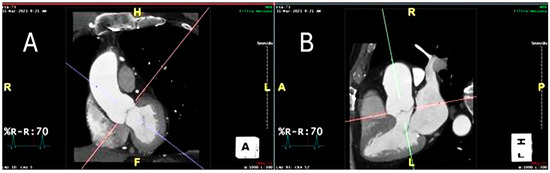

2.4. Technical Steps Required to Measure Perivascular Adipose Tissue Attenuation of the Proximal Ascending Thoracic Aorta on Chest Computed Tomography Angiograms